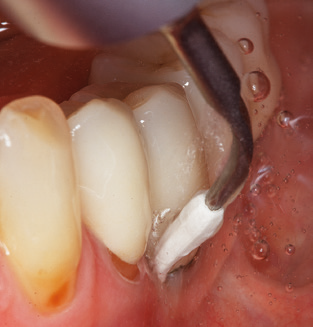

Good illumination of the working field facilitates the process considerably. The system used by the authors achieves this thanks to a 5x LED ring integrated in the handpiece. Naturally, a range of working tips for different indications is also offered. A straight, universally employable tip is the basic instrument required for machine cleaning of natural teeth (Fig. 5a and b). Curved tips, which allow access to exposed furcations, are also available for hard-to-reach areas in the posterior region (Fig. 6).

Of course, working tips for the cleaning of implant surfaces are also indispensable for SPT in patients fitted with implants. The implant cleaning attachment on the system used here is characterised by its tapered, hexagonal design. This design allows light, atraumatic penetration of the peri-implant pocket and displays a good cleaning performance (Fig. 7).

Fig. 4: Flexible probes with millimetre markings are recommended for the probing of dental implants (e.g. Colorvue Kit PCV11KIT6, Hu­Friedy). – Fig. 5a and b: A straight working tip (1P, W&H Dentalwerk Bürmoos GmbH) is a suitable instrument for use on all natural teeth. – Fig. 6: Curved working tips (3Pr/3Pl, W&H Dentalwerk Bürmoos GmbH) lend themselves to the processing of difficult-to-reach areas of the tooth and root surfaces (e.g. furcations). – Fig. 7: The tapered, hexagonal implant cleaning tip (1I, W&H Dentalwerk Bürmoos GmbH) permits atraumatic and efficient cleaning of the crown and abutment surfaces. – Fig. 8: Titanium and carbon curettes are suitable instruments for the manual cleaning of the implant surfaces.